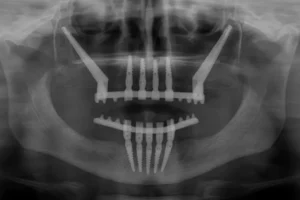

Impianti zigomatici in Albania: soluzione per chi ha poco osso Molti pazienti italiani si sentono dire che non possono mettere impianti dentali perché non hanno